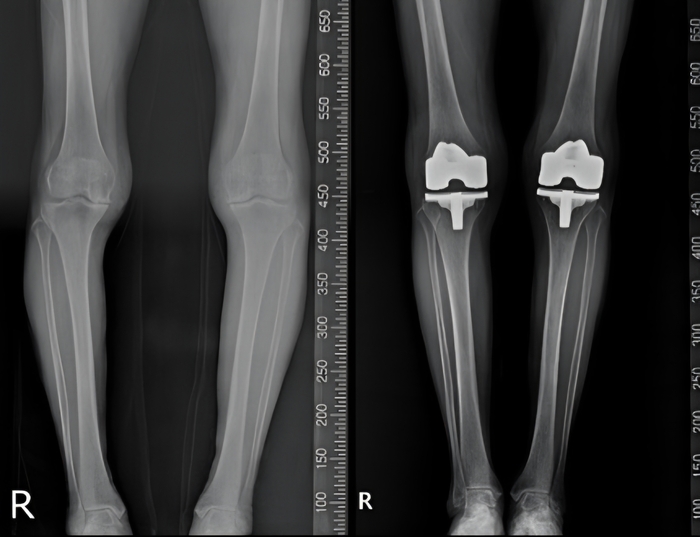

▲80대 여성을 대상으로 이뤄진, 니비게이트 AI인공관절수술 시스템을 접목한 무릎인공관절 치환술 수술전(왼쪽)과 수술 후 영상. 사진=연세사랑병원

18일 연세사랑병원에 따르면, 니비게이트는 수술 전 환자의 MRI 및 영상 데이터를 기반으로 무릎 관절의 정렬, 뼈의 형태, 변형 정도를 정밀 분석해 수술 계획을 수립하는 시스템이다. 니비게이트 인공관절 수술의 핵심은 PSI(Patient Specific Instrument, 환자 맞춤형 수술 가이드)의 활용이다. PSI는 환자 개인의 해부학적 특성을 반영해 제작된 맞춤형 절삭 가이드로, 수술 중 뼈를 절삭하는 위치와 각도를 보다 정확하게 유도하는 역할을 한다. 이를 통해 기존 획일적인 수술 방식에서 벗어나 환자 개개인에 맞춘 정밀한 인공관절 삽입이 가능해진다.

니비게이트 플랫폼을 활용한 인공관절 수술은 △환자별 무릎 정렬과 관절 구조를 반영한 수술 계획 수립 △절삭 오차를 줄여 인공관절 정렬의 정확도 향상 △불필요한 연부조직 손상 감소 △수술 결과의 예측 가능성 향상 등의 장점을 갖는다. 이는 수술 후 무릎 기능 회복과 통증 감소, 인공관절의 장기적 안정성 측면에서도 긍정적인 영향을 줄 수 있다.

고용곤 병원장은 “퇴행성 관절염 환자는 같은 진단명이라도 관절 변형의 정도와 뼈의 형태가 모두 다르기 때문에 환자 맞춤형 수술이 중요하다"면서 “니비게이트 플랫폼과 PSI를 활용한 인공관절 수술은 환자의 해부학적 특성을 정밀하게 반영해 보다 정확하고 체계적인 수술을 가능하게 하는 것이 특징"이라고 설명했다.